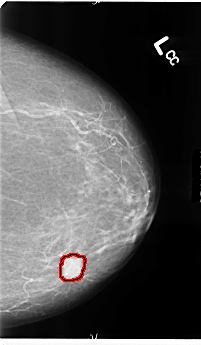

B_3108_1.LEFT_CC

LEFT_CC LINES 4824 PIXELS_PER_LINE 2808 BITS_PER_PIXEL 12 RESOLUTION 50 OVERLAY

FILE: B_3108_1.LEFT_CC.OVERLAY

TOTAL_ABNORMALITIES 1

ABNORMALITY 1

LESION_TYPE MASS SHAPE ROUND MARGINS SPICULATED

ASSESSMENT 4

SUBTLETY 5

PATHOLOGY MALIGNANT

TOTAL_OUTLINES 1

BOUNDARY